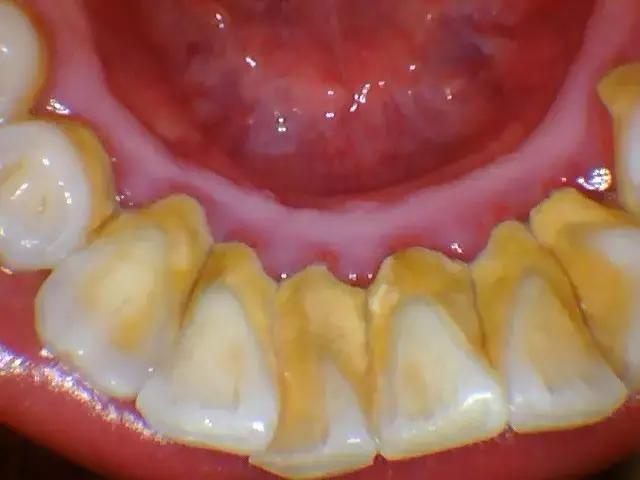

牙结石几乎每个人都有。在我国,由于国人的口腔保健意识比较淡薄,因此对于牙结石的存在,很大一部分人基本上是忽略的,认为牙结石没什么大不了的,殊不知,牙结石是牙周病菌的主要载体,由它引起的牙龈疾病往往是一发不可收拾。一般情况下,牙结石呈现出黄白色、棕色、或者黑色。

龈上牙结石,也叫可见牙结石,一般是覆盖在牙缝,牙背,牙根部,肉眼能看到;

1、对着镜子看,如果发现牙根,牙缝,牙背有一层黄色,棕色或者黑色的东西,一般就是牙结石;